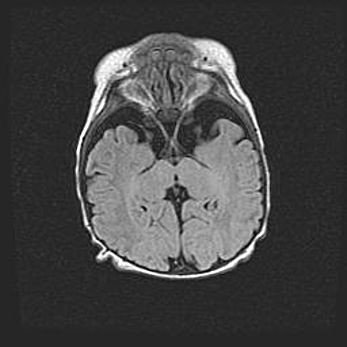

Открытая гидроцефалия.

Возраст: 9 месяцев 12 дней

Вес: 6800 г

Пол: мужской

Окружность головы: 41,5 см

Срок гестации: 28 недель

Гидроцефалия головного мозга у новорожденных имеет характерный признак: опережающий рост окружности головы приводит к визуально хорошо определяемой гидроцефальной форме сильно увеличенного в объёме черепа. Детские неврологи определяют следующие симптомы гидроцефалии у грудничков: выбухающий напряжённый родничок, частое запрокидывание головы, смещение глазных яблок к низу.